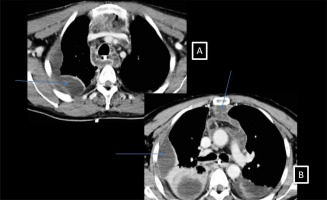

Figure 1

A–C – Transversal views of a rhino cervical scan with multiple beginning infectious collections